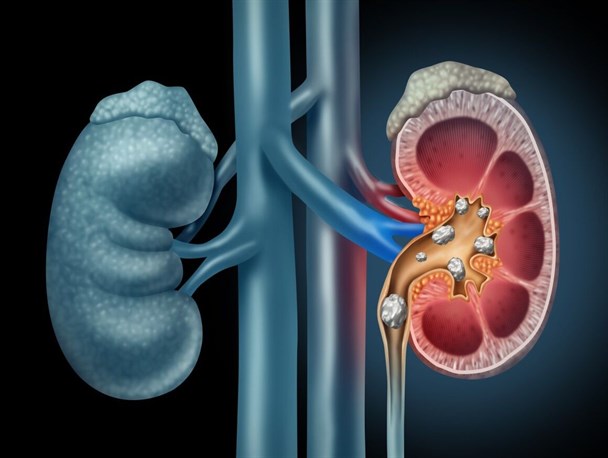

,وی ادامه داد: سنگ کلیه به ذرات کوچک و سختی در کلیه گفته می شود که بیشتردر دهه های چهارم و پنجم زندگی فرد را درگیر می کند و کسانی که سابقه خانوادگی سنگ کلیه دارند ۲ برابر دیگر افراد در معرض ابتلا به سنگ کلیه هستند.

,وی در مورد نارسائی های کلیه گفت: کلیه ها دو عضو لوبیایی شکل با میلیون ها واحد فیلترکننده بنام نفرون هستند که وظیفه دفع سموم و جذب مواد مغذی و شیمیایی لازم برای متابولیسم بدن را برعهده دارند در صورتی که حدود ۹۰ درصد از نفرون ها از بین بروند، فرد در فاز انتهایی نارسایی کلیه قرار می گیرد و نیازمند دیالیز می شود.